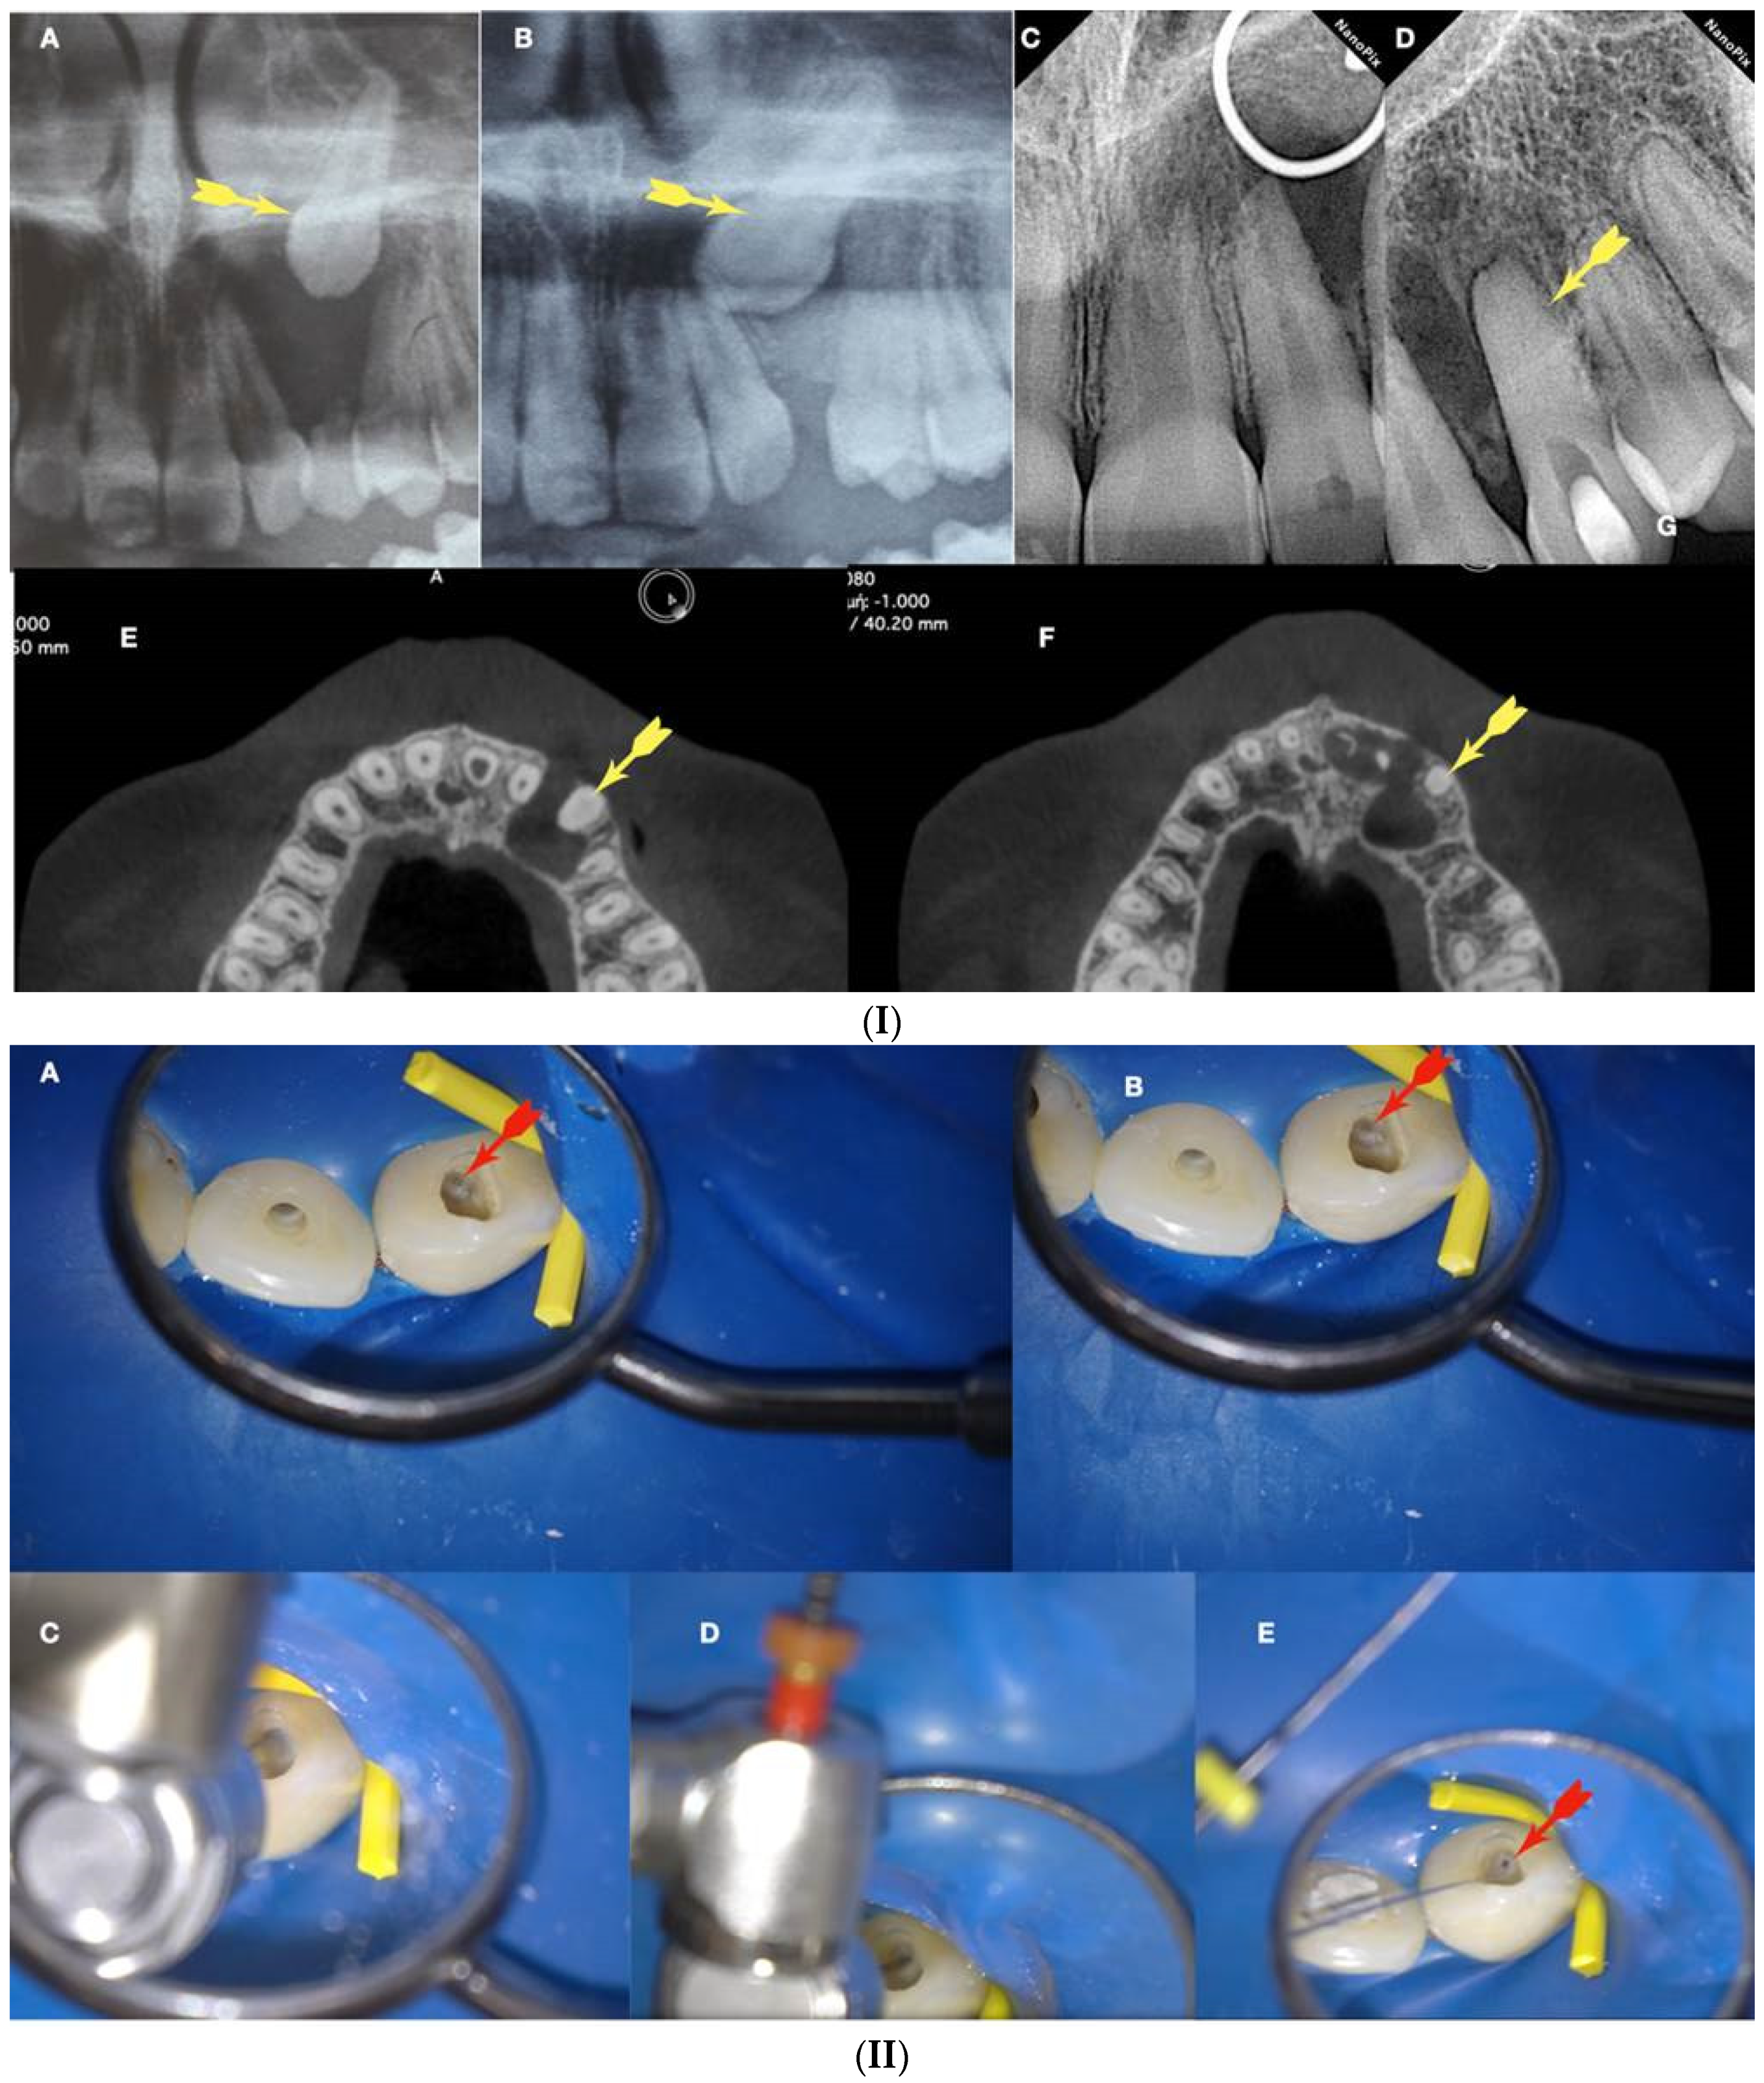

Figure 11.

(I) (A) Preoperative panorax focused on the impacted right maxillary canine, revealing a large lesion. (B) Two-year follow-up panorax after the surgical removal of the lesion revealing healing. (C,D) Periapical radiographs reveal recurrent disease 6 years after the surgical intervention. Notice that the maxillary canine was brought in occlusion with orthodontic treatment, but the canal was rendered radiographically blocked. (E,F) CBCT axial slices evaluate the magnitude of the periapical lesion and the root canal calcification of the maxillary canine. (II) (A,B) Clinical microscopic image from two different angles of the previously initiated access cavities. Notice the gray spot indicating the calcified root canal orifice (yellow arrow). (C) Clinical image of the initial troughing of the calcified canal with a round long shafted bur (Munce bur). (D) EDM file during the buckling resistance activation test negotiation technique. (E) Clinical image of the calcified orifice after the first BRAT stroke. Canal negotiation with the 08 D-finder file is now possible. (III) A Preoperative periapical radiograph. (B) Periapical radiograph demonstrating the initial negotiation of an 08 D-finder after the first BRAT stroke. (C) Periapical length determination radiograph. (D) Postoperative radiograph. (E) One-year follow-up periapical radiograph. (F–H) Three-year follow-up cbct reveals complete healing of the periapical lesion (axial slices) (clinical images and radiographs courtesy of Dr. Chaniotis Antonis). Red arrows indicate the calcified canal location, and Yellow arrows indicate the impacted canine. The white circle is the projection of a nose piercing ring in the radiograph (not a symbol).